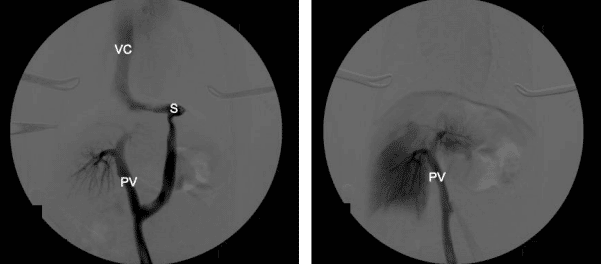

The aim of surgery is to close the shunt and restore normal portal blood flow to the liver and hence normal liver function. In an ideal world, all shunts would be completely closed at the time of surgery. However, complete shunt closure is not possible in approximately 50% of dogs with extrahepatic CPSS as the liver and portal venous system are hypoplastic and cannot tolerate normal portal flow leading to portal hypertension. For this reason, gradual attenuation devices have been developed to allow complete shunt closure without the risk of portal hypertension. These include ameroid constrictors and thin film bands. These are placed around the shunt and provide gradual closure over a period of weeks. However, one disadvantage of these devices is that once they have been placed there is no control over the rate or completeness of closure. This can lead to persistent shunting if the device fails to close the shunt completely or if the shunt closes too rapidly, resulting in MAS. Persistent shunting is reported in 24- 37.5% of dogs. At Paragon we tailor the surgical treatment to the individual dog and their owners. We believe that the overall goal of shunt surgery should be to completely close the abnormal vessel either gradually or acutely, in order to abolish all shunting and give the dog the best possible outcome. We perform intraoperative mesenteric portovenography in all dogs during surgery to help identify the shunt and assess the degree of portal development. Dogs are assessed during the surgery to see if they can cope with full closure of the shunt (based on subjective and objective assessment of portal pressures and the degree of portal development on IOMP). Complete ligation is performed in dogs that can tolerate it and those that can’t have placement of an ameroid constrictor or thin film band. A length of suture is left around the shunt in order to facilitate any future surgery if persistent shunting is subsequently identified.

congenital portosystemic shunt (CPSS). The image on the left shows the majority of blood flow is

through the shunt, with some opacification of the portal vein and intrahepatic vasculature. The image on the right shows increased opacification of the intrahepatic vasculature and no contrast flow through

the shunt, following complete closure. VC = vena cava, PV = portal vein, S = shunt.